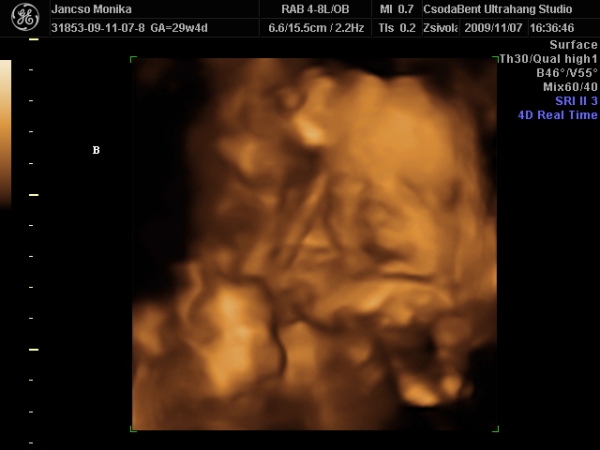

Na voltunk 4d-n mégis, a minimanóban ahol kiderült, hogy a szonográfus meg a férjem ismerik egymást, szóval biztos vagyok benne, hogy mindent megpróbált, de nem lettek jó képek talán 2 héttel korábban kellett volna mennünk

azért rakok be képeket